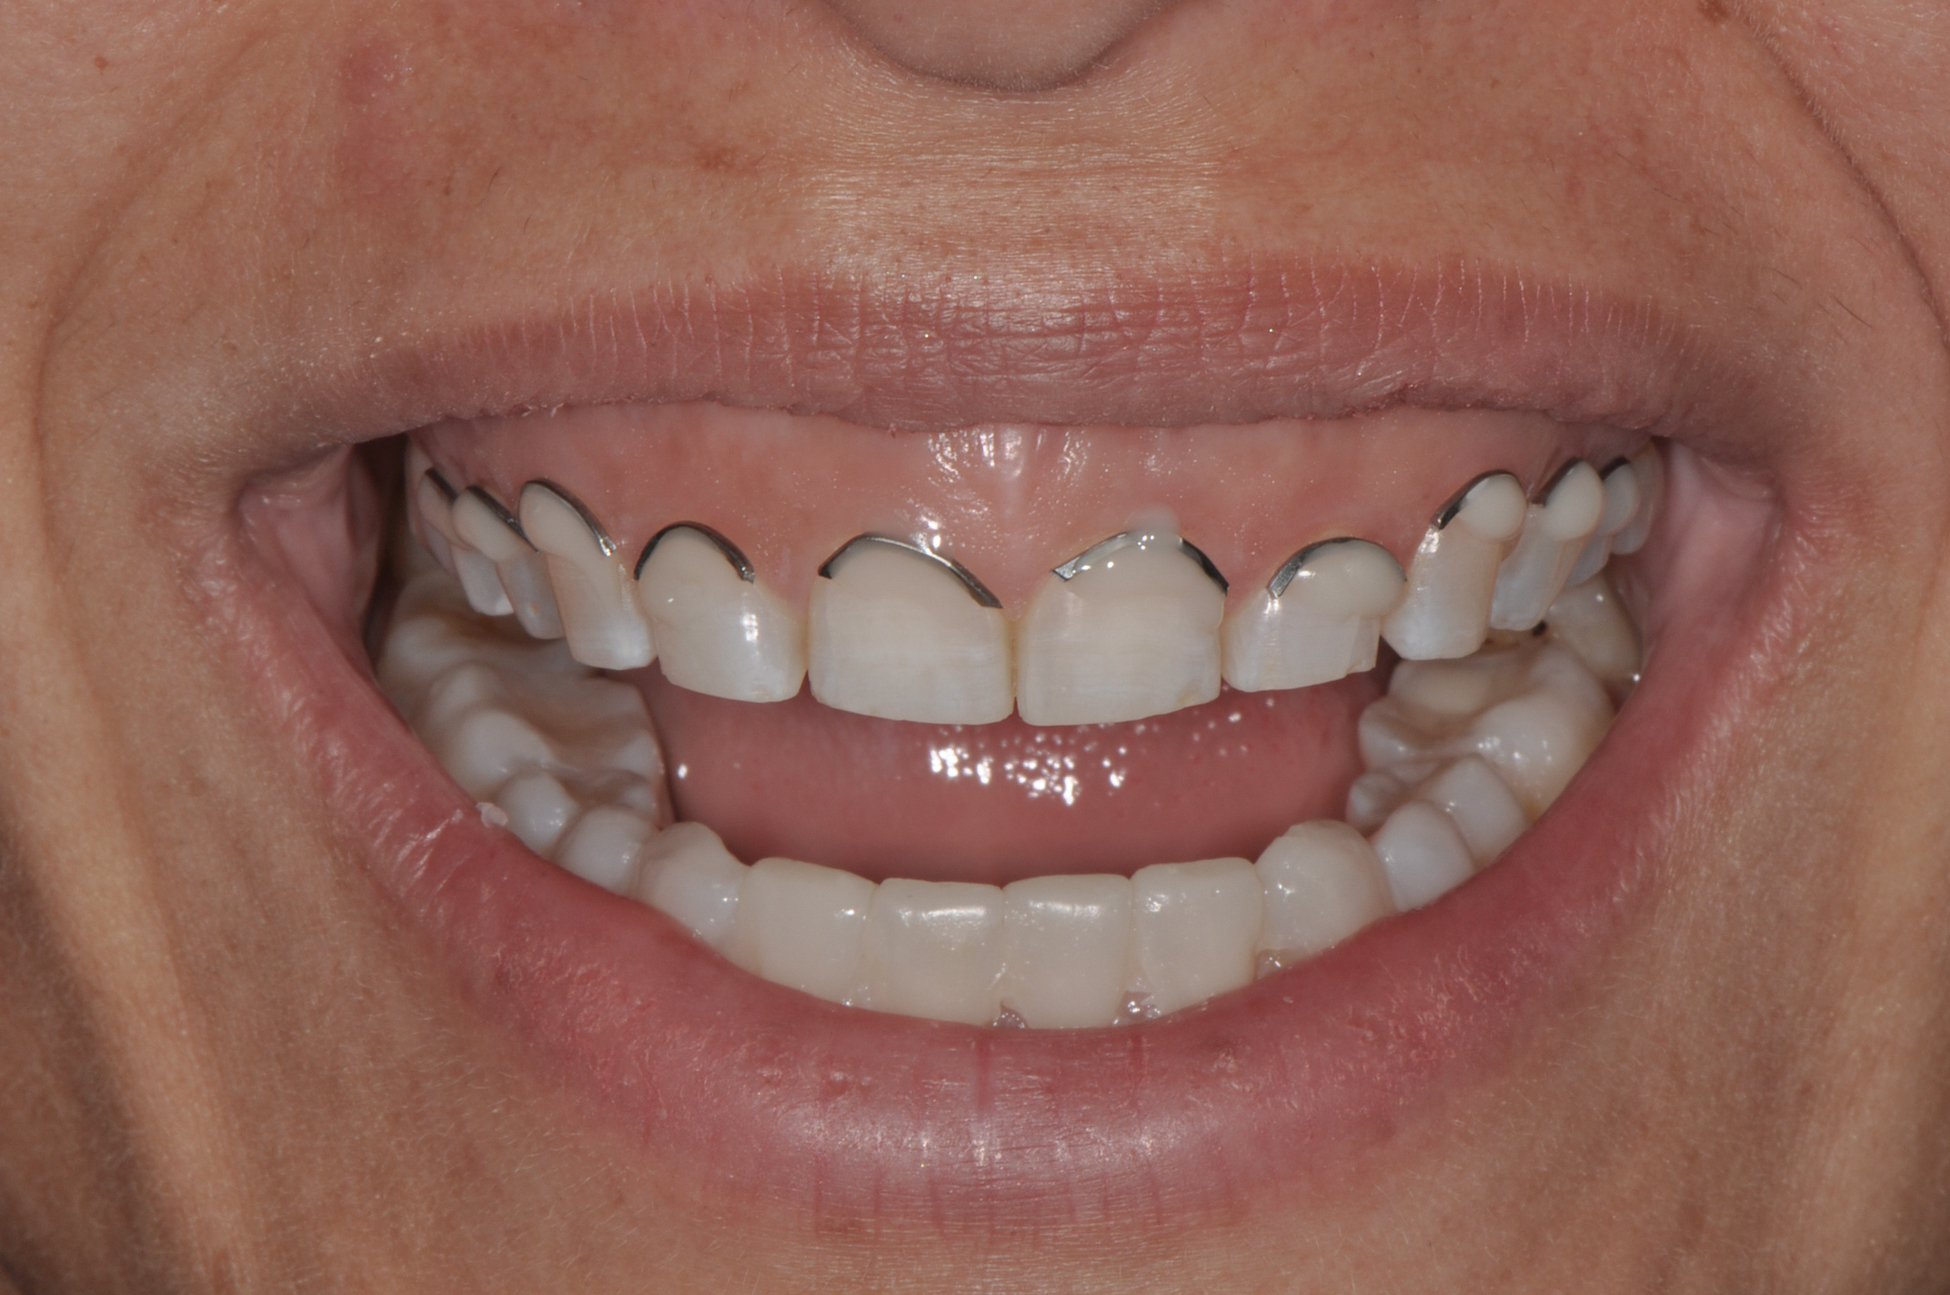

Smile line assessment is a validated process that is used for esthetic evaluation.1 Gummy smile (GS) has been defined as a nonpathological condition causing esthetic disharmony in which more than 3 mm of gingival tissue is exposed when smiling2 (Figure 1). The possible causes are excessive maxillary growth, short upper lip, or abnormal eruption of maxillary anterior teeth. Subsequently, short tooth syndrome (STS) has been defined as a condition caused either by excessive gingival display or lack of incisal tooth display during smiling or a low smile line.3

Fig 1. Patient with a gummy smile.

Figure 1

Fig 2. Resolution of gummy smile after treatment in patient shown in Fig 1.

Figure 2